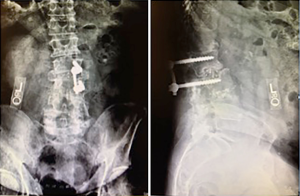

On postoperative day 1, the patient had flatus, his diet was advanced, and he did have a small bowel movement. On postoperative day 2 the patient had severe abdominal pain and distension with hypoactive bowel sounds. At this point, the general surgery service was consulted. No abnormalities were noted in his laboratory values. Radiographic findings (Figure 2) were consistent with postoperative ileus with no evidence of obstruction or pneumoperitoneum. He received bisacodyl suppositories, was encouraged to ambulate, and started on a clear liquid diet.